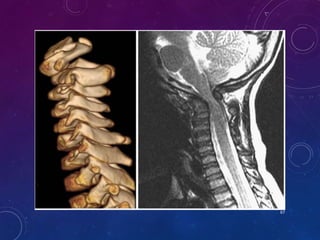

C1

ODONTOID AGENESIS

40

41

42

• #40 a/w spondylometaphyseal or spondyloepiphyseal dysplasia Fig: T1 MRI Agenesis of apical dental segment, with a slightly short dental pivot but a definite basal segment (pointed) and a lower dental synchondrosis (LS). Arrow points to anterior arch of C1. Note platybasia and Chiari I malformation

• #41 Lateral radiograph shows complete absence of odontoid process. Midsagittal T1 MRI of brain and cervical spine. The cervicomedullary junction is atrophic.

• #42 Complete agenesis of the dens in a 10-year-old child with spondyloepiphyseal dysplasia. a CT sagittal and coronal views show no dental pivot Although the centrum with a flat top does rise up above the “expected” level of the lower dental synchondrosis.

• #43 3-D CT reconstruction and MR show the flat top of the centrum and potential for instability